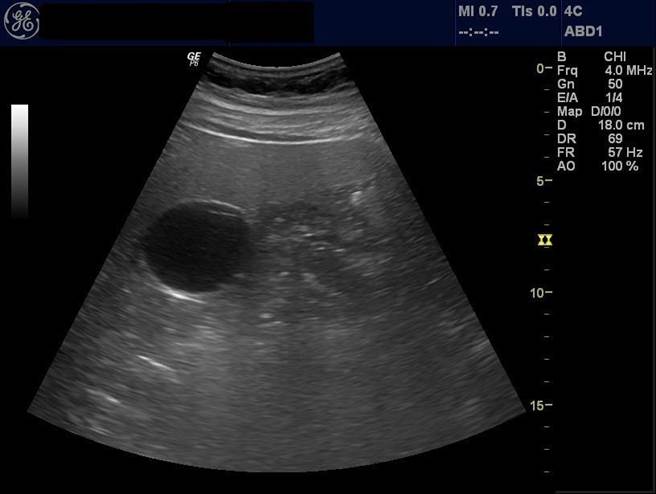

曾晟恩指出,蔡先生抽血检验发现GOT/GPT指数高达415/159 U/L(正常值在40 U/L以下),超音波检查发现有重度脂肪肝,胆固醇指数也异常。若没有积极改善,未来恐导致各种疾病上身,为鼓励蔡先生消脂保肝,他主动约定一起调整饮食和培养运动习惯。